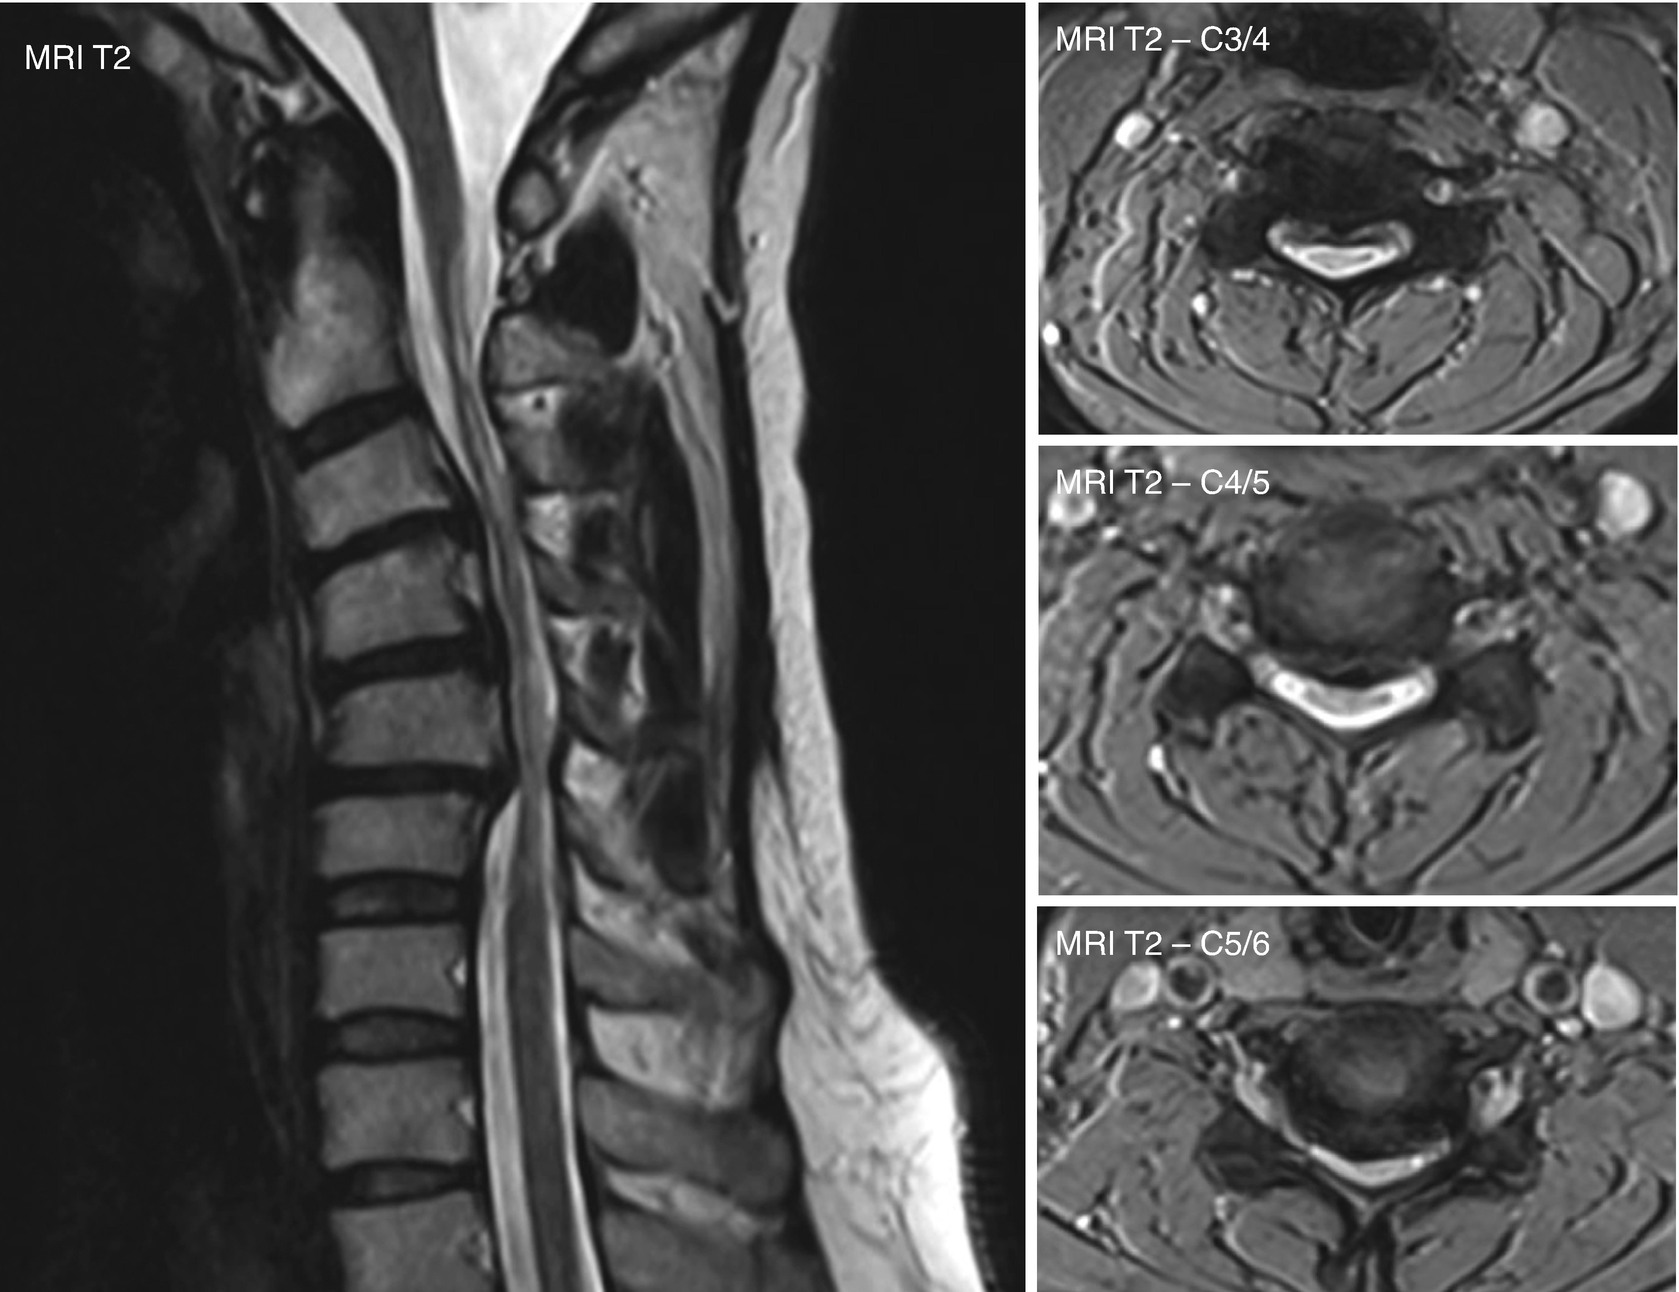

Mri Of The Cervical Spine Of A Patient With Ntsci Due To Degenerative Download Scientific Diagram